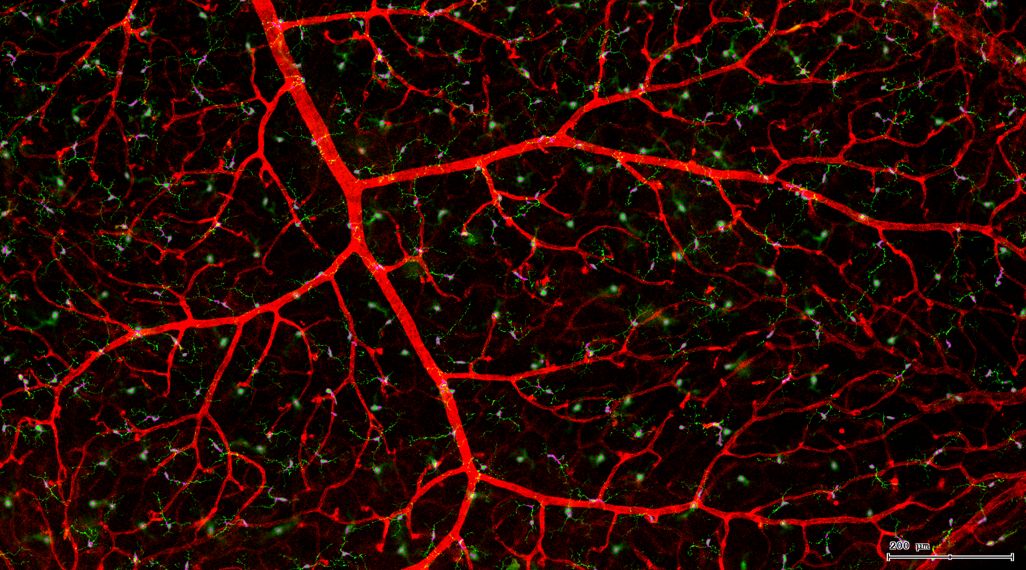

视网膜血管作为人体内唯一可以进行非创伤直接观察的深层微血管,其生理状况的检查对高血压、糖尿病、动脉硬化等心血管疾病的诊断、治疗评价具有重要意义。

一般而言,眼底图像通常都是通过激光扫描成像进行采集,但是由于眼底可观测的视野往往是很有限的,一个患者的眼底信息需要多张扫描图像才能完全显示出来。这种局限性大大不利于病情进行全面的、细致的诊断。Tissue Cytometry全景组织流式定量分析技术进行全景图像获取,在单细胞、组织结构、细胞空间信息等多个层面进行定位、定性、定量分析。从而更好的对病变区域进行有针对性的跟踪观察和全面分析。

视网膜荧光样本中小胶质细胞胞体、神经纤维识别、血管识别、血管斑点识别、神经元与血管的距离分析。

1. 利用TissueFAXS系统进行玻片荧光的全景扫描。

5. 识别血管的Texa Red染色区域面积及强度。

血管识别:根据Texa Red通道进行识别,并去除面积小的及非同一焦面的血管,仅对确定的清晰的同一焦面的大血管进行面积统计。